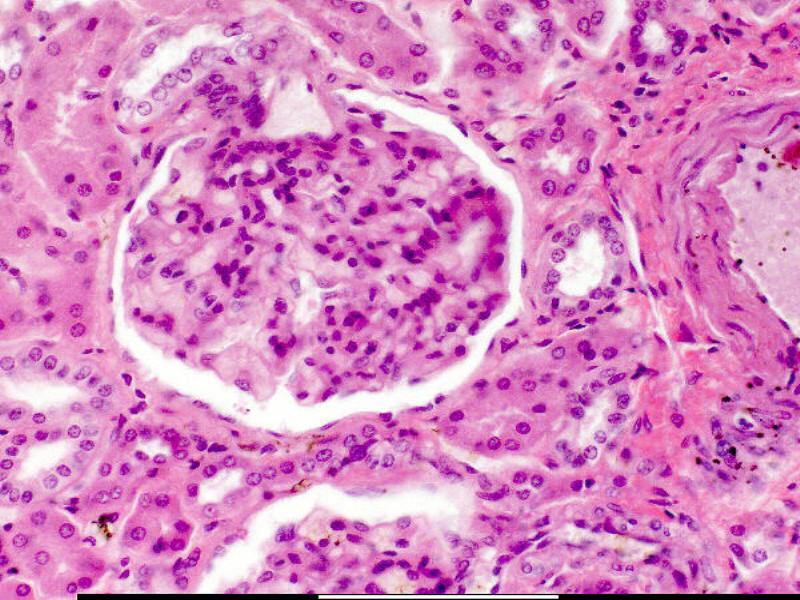

What can you identify on the next slide?

Make a list before advancing.

Cuboidal epithelium is associated with ducts. The kidney consists of ducts, most of which are lined with cuboidal epithelium.